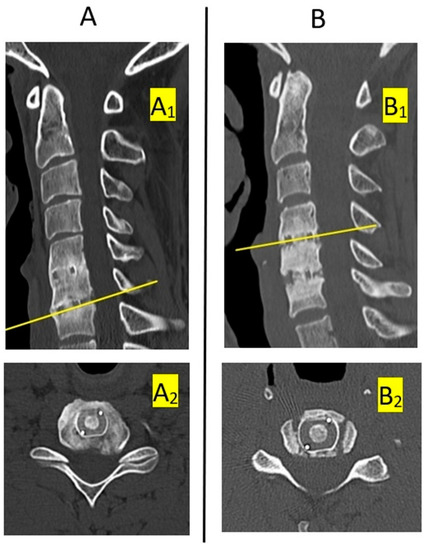

| Computed tomography images | Continuity of bone tissue immediately anterior, posterior, medial and lateral to implant on CT scan | Visible bone tissue continuity | No continuity of bone tissue | No continuity of bone tissue |